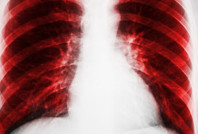

Akciğer hastalarının dikkatine: Bu üç şarkıyı söylemek iyi geliyor Yeni bir araştırma, akciğer hastalıklarına sahip kişilerin Elvis Presley ve The Beatles'ın şarkılarını sesli bir şekilde söylemesinin faydalı olabileceğini gösterdi.